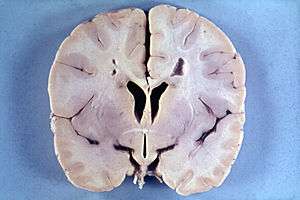

Brain of a 4-year-old boy with Alexander disease showing macroencephaly and periventricular leukomalacia (note brownish discoloration around the cerebral ventricles) | |